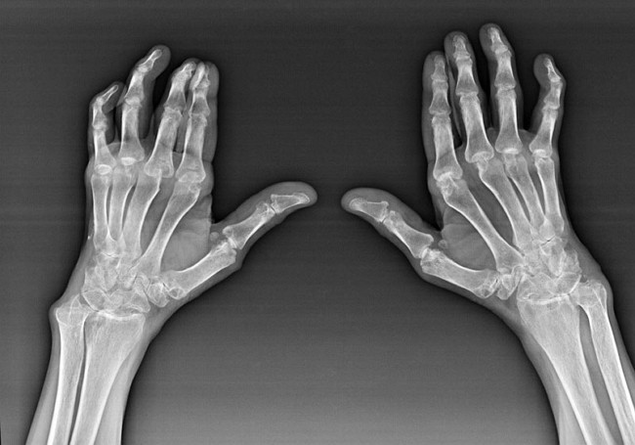

Artritis erreumatoidea gizakiaren sistema immunologikoak gorputzaren ehunak kaltetzen dituen gaixotasuna da. Beste modu batera esanda, artritis erreumatoidea patologia autoimmune bat da. Gaixotasun hau ere sistemikoa da, ehunek horiekin kaltetuta baitute (muskuluak, artikulazioak, ontziak, etab.) eta organoak (Bihotza, giltzurrunak, birikak eta abar.) gorputzean.

Artritis erreumatoidea haren azpian dagoen gaixotasun sistemikoa izan arren, artikulazioek jasaten duten arren, beste ehun eta organoen lesioa atzeko planoan dago. Gaixotasun honekin, ia eskuila juntura mota guztiak izan daitezke (Eskumuturrekoak, Carpal-Paths, Metacarpal-Phalanx, Phalanxen arteko artikulazioak). Lesioa simetrikoa izan ohi da (horiek. Artikulazio berdinak kaltetuta daude) bi eskuetan, hantura, mina kaltetutako artikulazioetan lagunduta. Goizean, ohetik altxatzean, kaltetutako artikulazioetan zurruntasun batzuk daude, ordubete inguru iraun dezakeena eta arrastorik gabe desagertzen dena.

Nahiko maiz artritis erreumatikoarekin eskuila kaltetutako artikulazioetatik gertu (maizago piano-falange, phalanx arteko artikulazioetan) Nodules erreumatoideak agertzen dira. Larruazalaren azpian kokatutako eraketa biribilduta daude. Eskuila gainean, formazio hauek maiz agertzen dira atzeko aldean. Palpazioan, trinkoa, inaktiboa eta minik gabea da. Horietako kopurua aldatu egin daiteke.